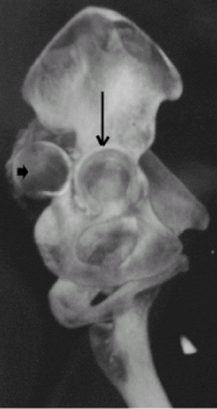

Evaluation of anatomically complex areas, such as pelvis, scapula, wrist, ankle, and spine (Fig. 2)

Fig.

2. Sagittal oblique volume-rendered 3D CT image of the pelvis shows

posterior dislocation of the right hip. The femoral head (short arrow) and empty acetabular fossa (long arrow) are marked. -